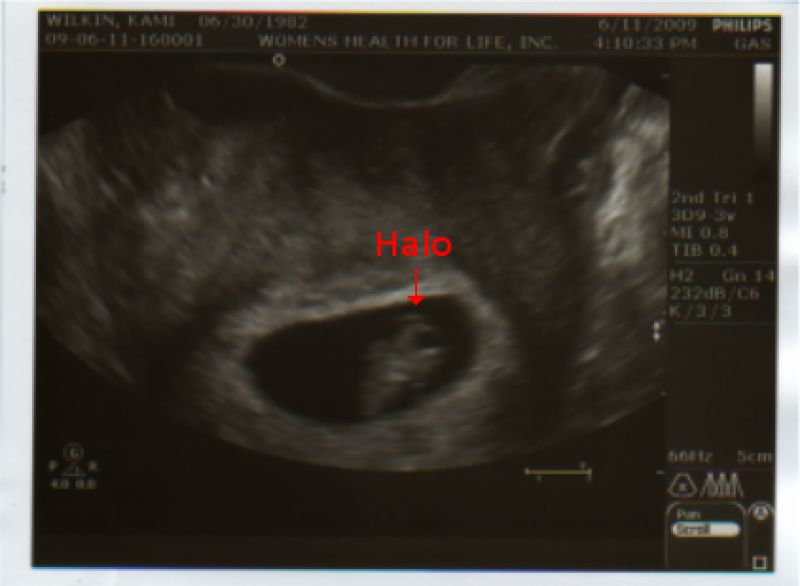

7 Week Ultrasound

You would never guess that 7 weeks are past by now and our first ultrasound has been taken.  Imagine our delight when we found out our baby has a halo!  That must mean he/she has angels for parents (we can't see how it could be described any other way).  If you do not believe us, just check the photo for yourself.

The only further excitement was hearing the baby's heartbeat, and man were we glad to hear that (and yes, we only had one heartbeat, not two -- we are not sure what that says about the mom though...)  The baby is healthy,  and apart from the occasional morning sickness the mom is too.